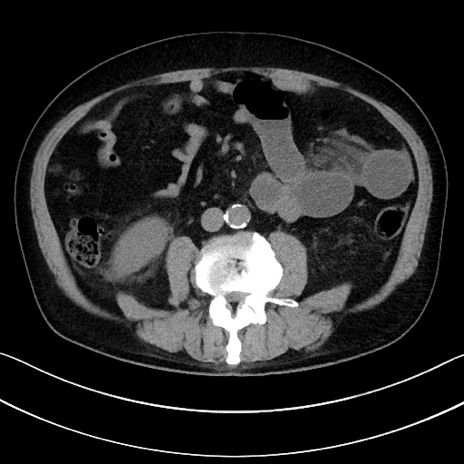

症例15(横断像)

【症例】70歳代男性

【主訴】腹痛

【現病歴】今朝から腹痛あり。全体的に痛い。特に左上の方。排ガスが今日はない。冷や汗が出る。

【既往歴】直腸癌術後

【身体所見】左側腹部〜上腹部に圧痛あり。腹膜刺激症状明らかなではない。軽度反跳痛。左下腹部に術後瘢痕あり。

【データ】WBC 7700、CRP 0.02